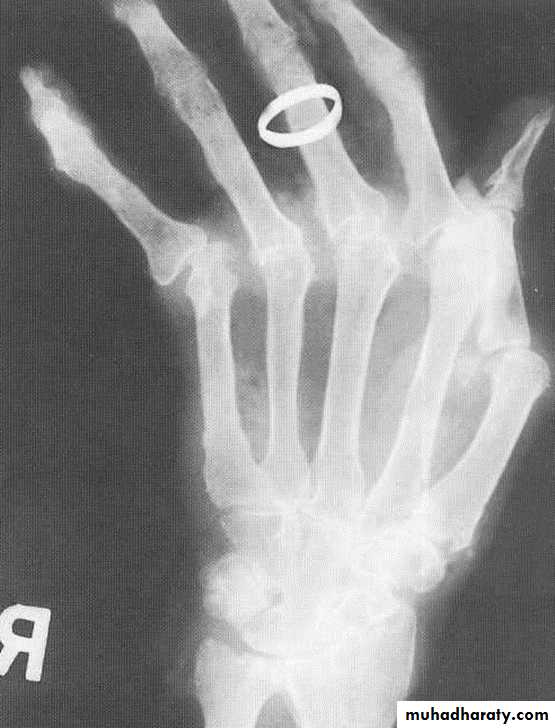

GOUT

Radiographic features:

Lower extremity > upper extremity; small joints > large joints

* First MTP is most common site

* Marginal, peri articular erosions: overhanging edge

* Erosions may have sclerotic borders

* Joint space is preserved

* Soft tissue and bursa deposition

Tophi: juxtaarticular, helix of ear

* Erosions and tophi only seen in longstanding disease

* Tophi calcification, 50%